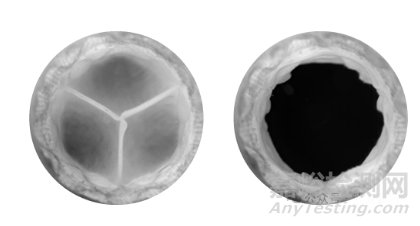

心包瓣葉

豬心包瓣葉在右心的整個(gè)壓力范圍內(nèi)提供出色的運(yùn)動(dòng)學(xué)。

豬心包組織瓣膜

自膨脹鎳鈦合金框架

滌綸布覆蓋物